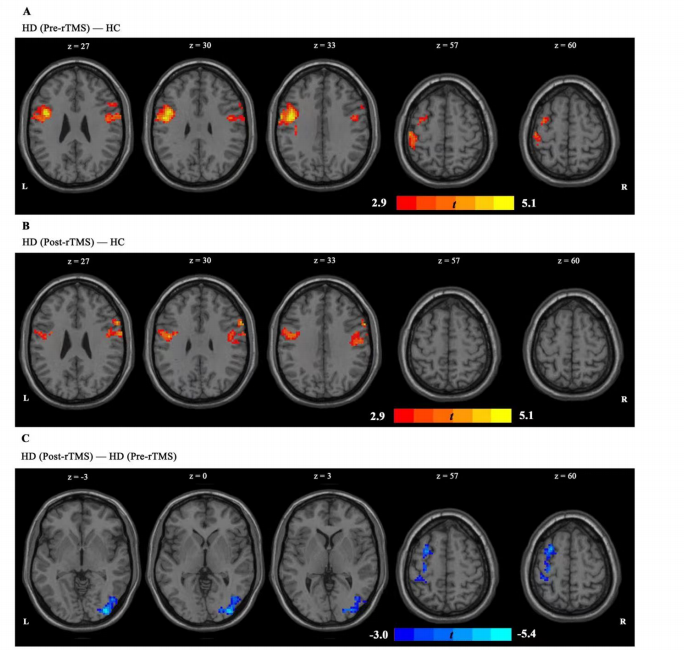

上圖為經(jīng)顱磁刺激后左側(cè) IPL 與全腦網(wǎng)絡(luò)之間的功能連接,采用雙樣本t檢驗(yàn)。A圖顯示,與 HC組相比,HD(治療前)組左側(cè)IPL-左中央前回偶聯(lián)和左側(cè)IPL-右額下回耦聯(lián)增加。B圖顯示,經(jīng)rTMS治療后,HD組左IPL-左中央前回耦聯(lián)和左IPL-右額下回耦聯(lián)異常增加明顯減少,在完成 7 個(gè)療程的 rTMS 治療后,呈接近HC組的趨勢(shì)。C圖顯示 rTMS 對(duì)左側(cè)IPL-左側(cè)額中回偶聯(lián)和左側(cè)IPL-右側(cè)枕下回耦聯(lián)有顯著影響。在這兩個(gè)區(qū)域,經(jīng)過(guò) 7 次經(jīng)顱磁刺激療程后,功能連通性顯著下降。

上圖為經(jīng)顱磁刺激后右側(cè) IPL 與全腦網(wǎng)絡(luò)之間的功能連接。

A圖顯示,HD組(治療前)的右側(cè) IPL-左側(cè)中央前回偶聯(lián)和右側(cè) IPL-右側(cè)中央前回偶聯(lián)均有所增加。B圖顯示,在 7 個(gè)療程的經(jīng)顱磁刺激后,這些異常增加的連接減少了